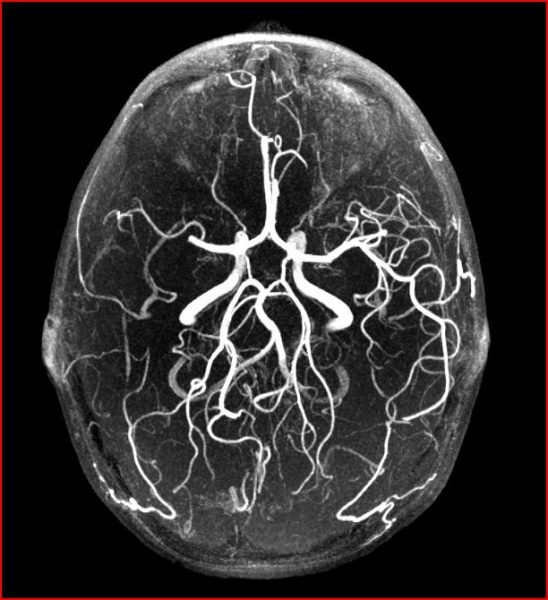

Η έμπειρη διεπιστημονική ομάδα του Κέντρου, διαπίστωσε απόφραξη της αρτηρίας που αιματώνει το αριστερό μέρος του εγκεφάλου, το οποίο είναι υπεύθυνο για την ομιλία και τη λειτουργία της δεξιάς πλευράς του σώματος. Χορηγήθηκε θρομβολυτικό φάρμακο, ενώ πραγματοποιήθηκε και μηχανική διάνοιξη της αρτηρίας, κατά την οποία αφαιρέθηκε ο θρόμβος (πήγμα αίματος) μέσω επέμβασης που ονομάζεται θρομβεκτομή.

- Συνολικά, από την έναρξη λειτουργίας του Κέντρου έχει εφαρμοστεί ειδικό πρωτόκολλο απεικόνισης του εγκέφαλου και των εγκεφαλικών αγγείων σε περισσότερους από 300 ασθενείς.